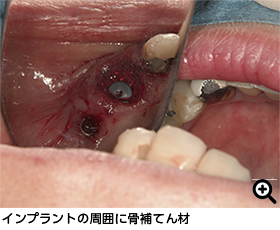

顎の骨が虫歯や外傷のせいで大幅にない場合は、骨をふやす手術をおこなっていますが、その際に用いる材料は骨補てん材といい、リン酸カルシウムを使っています。この骨補てん材は、何か月かで生体内で吸収され、骨再生を促してくれます。体にとってやさしい材料を用いています。

当院では骨の再生を行っており、骨が薄い状態でも十分に骨を再生させてからインプラントを入れています。

当院では骨の再生を行っており、骨が薄い状態でも十分に骨を再生させてからインプラントを入れています。

(骨が陥没した状態から治療しました)